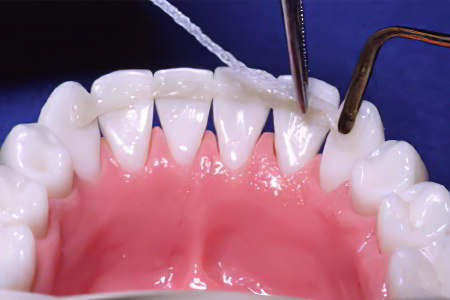

3. Ручная чистка. Зубы обрабатываются специальным инструментом с крючком на конце. Стоматолог аккуратно удаляет камень, находящийся под дёснами. Этот метод используется реже, так как считается устаревшим, но его можно комбинировать с ультразвуковой чисткой для повышения эффективности.

Удаление зубного налёта